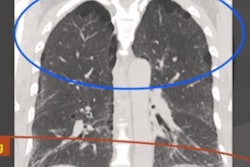

The researchers used version 15.6 of the Eclipse radiotherapy planning software (Varian Medical Systems) to perform volumetric analysis of images from the patients' initial CT exams.

"We choose radiation oncology software due to the enhanced structure delineation capability in three planes (axial, coronal, and sagittal), real-time tridimensional reconstruction, and the precision of the volumetric measurement tools," they wrote.

Two radiation oncologists with five- and 10-years' experience, respectively, performed contours of the lungs and the consolidations. The researchers then calculated the relative consolidation volume by dividing the volume of the lung consolidations by the total bilateral lung volume.